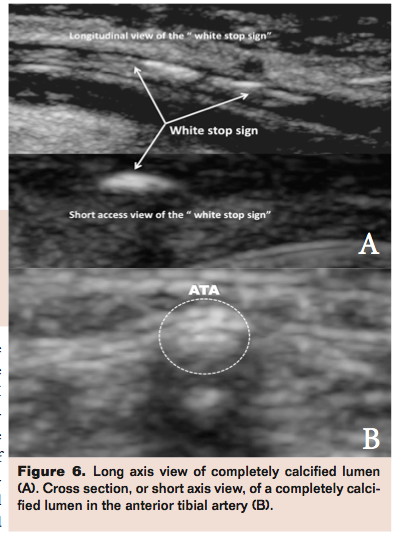

The distribution of calcium in the arterial wall is heterogeneous: there are different densities of calcium deposits in all four quadrants of a given arterial cross section that are randomly distributed in all three arterial layers. We have observed isolated intimal, medial, and adventitial calcium foci, which occur either independently or in random combinations. The presence of calcium in the arterial wall makes it resistant to the opposing force generated by the increase in barometric pressure offered by balloon inflations. The heterogeneous distribution of calcium densities is synonymous with a heterogeneous distribution of resistance, which during interventions leads to an unpredictable distribution of pressure vectors that follow the “path of least resistance” increasing the risk of dissection, plaque rupture and embolization with the ensuing “no-flow” phenomenon (Figure 5 depicts variations in calcification in the cross section of an artery. Figures 6A and 6B depict short- and long-axis views of fully calcified lumens).